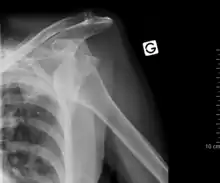

Anterior dislocation of the right shoulder. Y view X ray.

Fracture dislocation of the right shoulder